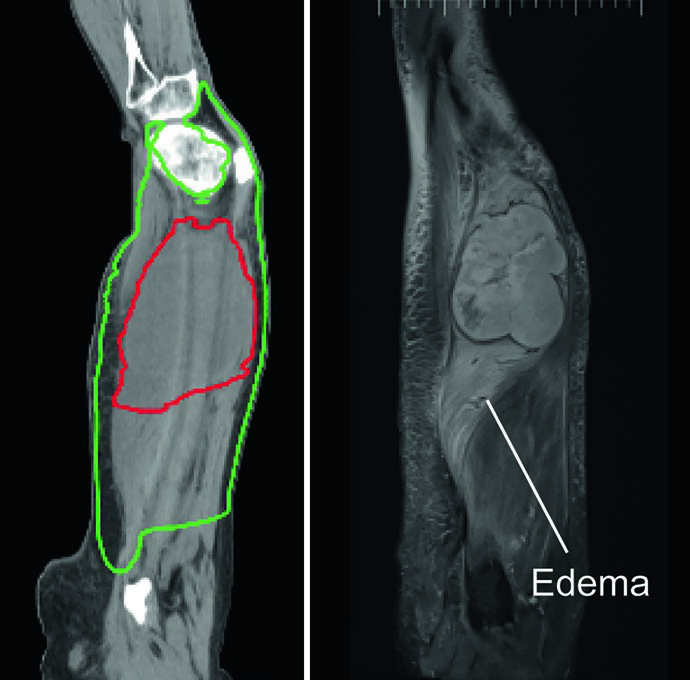

El edema peritumoral — mejor visualizado en secuencias T2 de resonancia magnética — puede albergar enfermedad microscópica y se extiende predominantemente en dirección craneocaudal. En la práctica habitual, este edema debe incluirse en el volumen blanco de radioterapia. Las barreras naturales a la diseminación tumoral, como hueso, membrana interósea y planos fasciales mayores, deben aprovecharse en la planificación para preservar tejido sano, especialmente en lesiones de extremidades.

Para la planificación preoperatoria, se debe realizar TC de simulación fusionada con RM, idealmente con el paciente en la posición de tratamiento. La RM con contraste T1 es la secuencia preferida para delimitar el volumen tumoral macroscópico (GTV), mientras que las imágenes T2 demuestran la extensión completa del edema peritumoral que frecuentemente se extiende varios centímetros en el eje longitudinal.

La dosis preoperatoria estándar es de 50 Gy en 25 fracciones de 2 Gy. El CTV50 debe incluir el GTV con un margen de 4 cm en dirección longitudinal y 1,5 cm en dirección radial, limitado por las barreras anatómicas a la diseminación tumoral (hueso, fascia). El edema peritumoral sospechoso debe contornearse por separado e incluirse con un margen adicional de 1 a 2 cm. El PTV añade 0,5 a 1,0 cm al CTV, según protocolos institucionales.

El edema peritumoral en sarcomas de extremidades puede alcanzar extensiones notables. Un caso ilustrativo del texto describe un mixofibrosarcoma grado 2 de muslo lateral con edema peritumoral masivo extendiéndose superior e inferiormente, resultando en un PTV de 42 cm — superando la capacidad máxima de campo para técnicas de isocentro único en la mayoría de los aceleradores lineales.

La solución empleada fue una técnica IMRT de doble isocentro, con los isocentros posicionados estratégicamente cerca del centro de cada subvolumen adyacente y cooptimizados para garantizar cobertura uniforme del PTV en la zona de unión. Esta situación refuerza la importancia de mapear completamente el edema en la RM T2 antes de la simulación: subestimar la extensión del edema compromete la cobertura terapéutica. La RM sagital resulta particularmente valiosa para delimitar la extensión craneocaudal.

Un detalle crítico: el CTV queda limitado por el hueso a lo largo de todo el volumen blanco. El SPB respeta barreras como hueso cortical y membranas interóseas, de modo que no es necesario expandir el volumen dentro del hueso. Este principio de preservación tisular reduce significativamente la toxicidad tardía. Para consideraciones adicionales en pacientes más jóvenes, consulte nuestro artículo dedicado al sarcoma pediátrico.